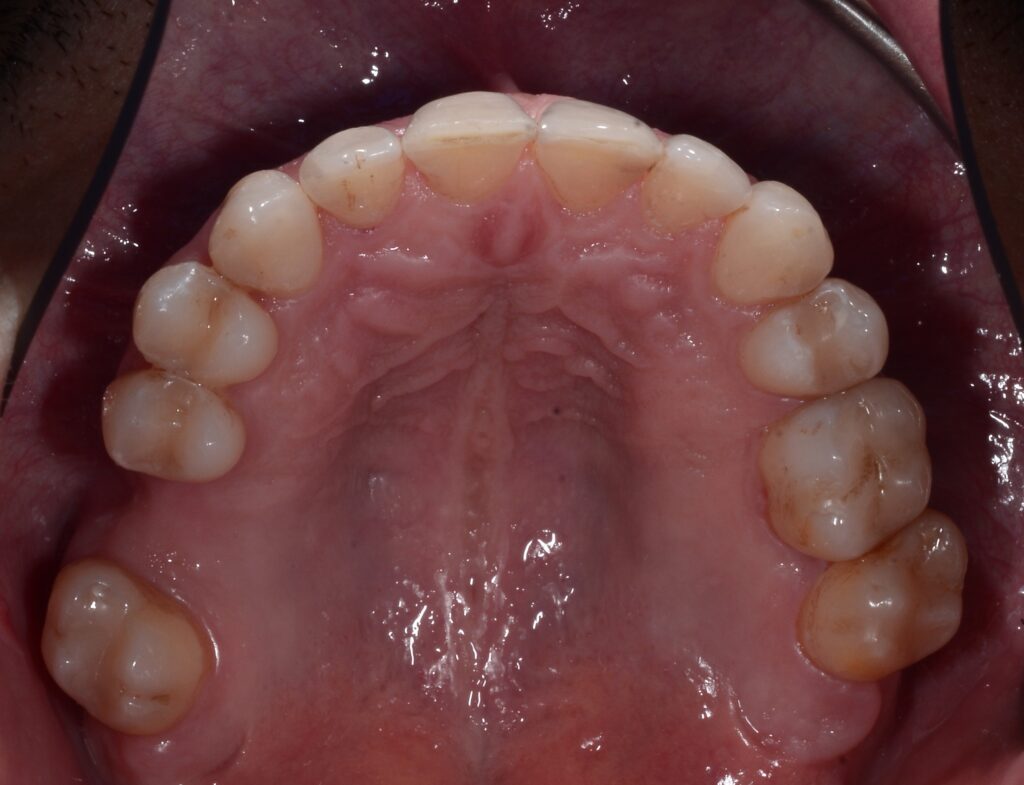

In this orthodontic case, Dr. Timpu-Dascalu addressed an anterior crossbite, a misalignment that can lead to functional issues and aesthetic concerns.

To correct the anterior cross-bite, the doctor utilized a comprehensive approach focusing on biomechanics to ensure precise tooth movement. This approach allowed her to achieve a stable and functional occlusion, improving both the patient’s bite and smile.

The treatment focused on correcting the anterior crossbite while simultaneously addressing both transversal and sagittal discrepancies. The primary goals were to expand both the upper and lower arches, derotate the molars, and address the uncontrolled tipping of tooth 12. Spark 20 package was selected to achieve the orthodontic goals. The treatment plan was meticulously developed using Spark’s Approver software.